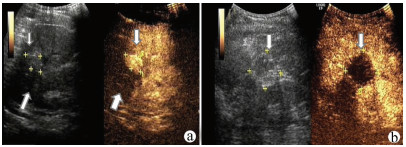

肝病超声诊断指南

中华医学会超声医学分会, 中国研究型医院学会肿瘤介入专业委员会, 国家卫生和健康委员会能力建设和继续教育中心超声医学专家委员会

2021, 37(8): 1770-1785. DOI: 10.3969/j.issn.1001-5256.2021.08.007

摘要(3068) HTML (6587) PDF (9311KB)(804)

超声检查无创、实时、价廉,无辐射、便于反复进行,是最常用的肝脏影像学检查方法。近年来,超声检查新技术如超声造影、弹性成像发展迅速,可有效鉴别肝内占位性病变性质、评估肝纤维化和门静脉高压程度以及监测肝病治疗效果,在临床肝病及其介入治疗中发挥重要诊断价值。本指南规范了肝病多模态超声技术(灰阶超声、彩色多普勒超声、超声造影、弹性超声)检查的仪器调置、患者准备及医生检查方法;对肝脏弥漫性病变(炎性病变、纤维化、硬化)、多种占位性病变及肝病介入操作的多模态超声技术诊断标准进行了定义和规范,同时推荐了超声监测周期及肝脏疾病超声诊断报告书写规范。